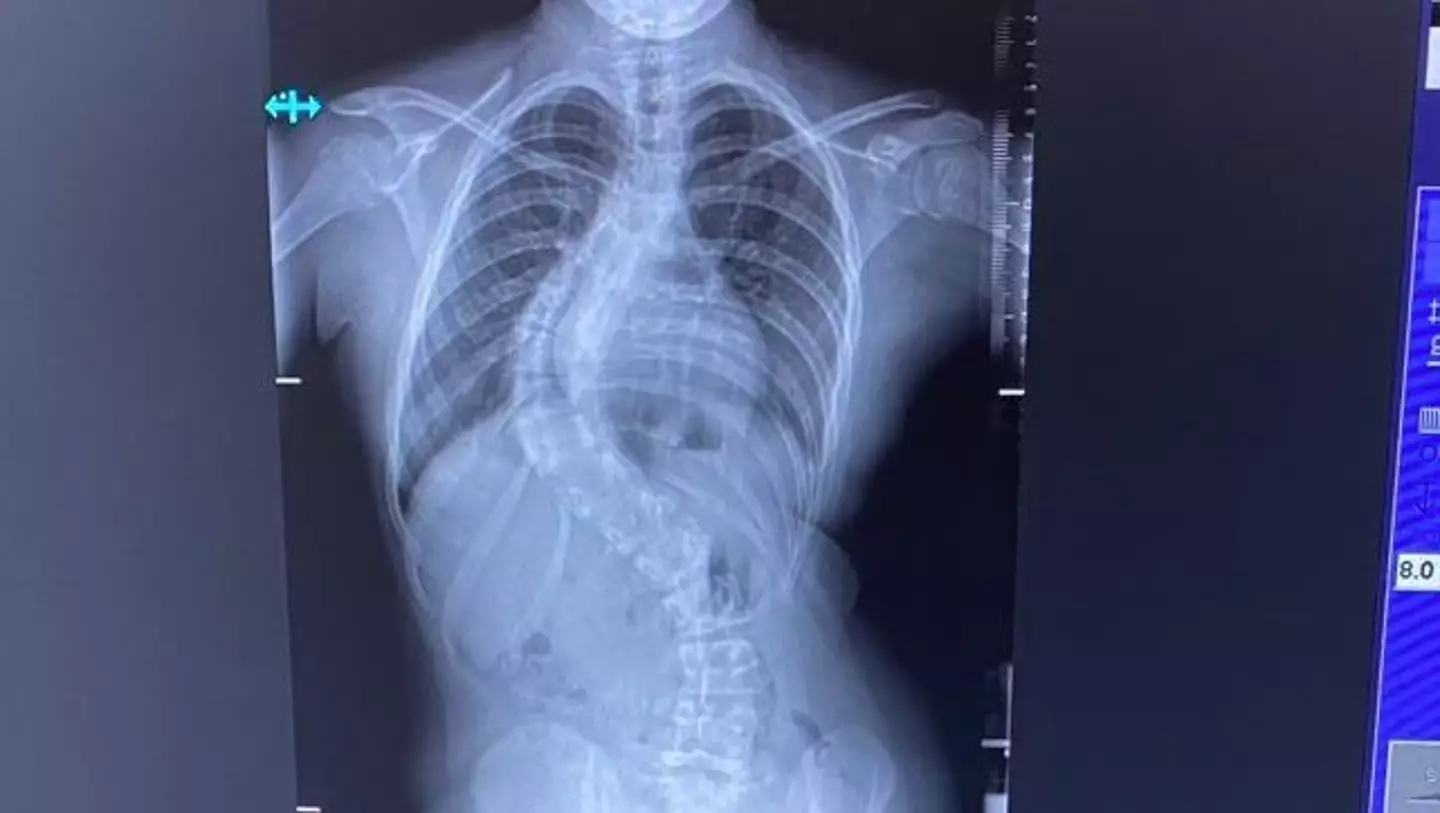

Heidi took Sophie to see a scoliosis paediatric consultant at Spire Manchester on 22 April where an x-ray revealed the curve to her spine.

The consultant told the family Sophie had rapid onset progression scoliosis.

"He said it's very severe though and it could be very problematic especially because of her age and how she's growing. We thought we might be able to get a brace but in her X-ray you can see her back is at an 80 degree bend which he said is way past the point of just having a brace.

"He said the only option was surgery as time is of the essence. If the bend starts going even further it can start crushing her lungs and heart. If it continues to grow and there's no intervention that's what can happen."